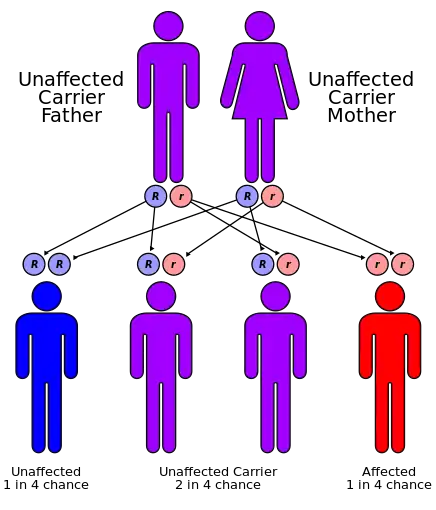

| Causes | Inherited[4] |

It is inherited as autosomal recessive, and causes an isolated increase of conjugated bilirubin in the serum.[5] The liver typically appears black due to the deposition of a pigment similar to melanin.[5] This condition is associated with a defect in the ability of hepatocytes to secrete conjugated bilirubin into the bile, and is similar to Rotor syndrome.[5] It is usually asymptomatic, but may be diagnosed in early infancy based on laboratory tests.[5] No treatment is usually needed.[5]

It is an autosomal recessive disease and is likely due to a loss of function mutation, since the mutation affects the cytoplasmic/binding domain.